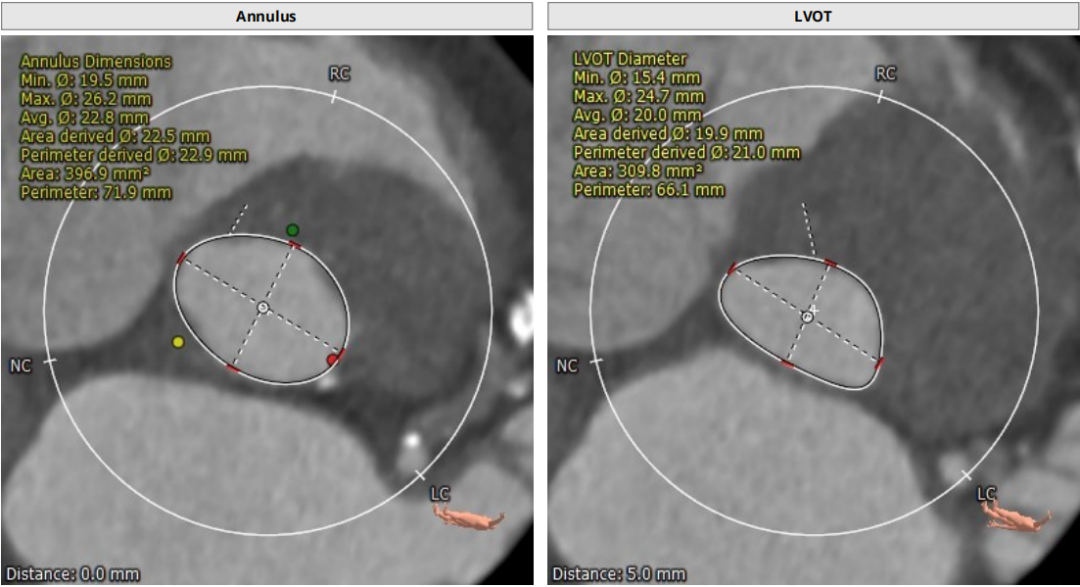

根部CT

三叶瓣,重度钙化,钙化主要分布在瓣叶游离缘,法式窦结构较大,双冠高度较高,升主动脉未见明显扩张,心脏角度40°,左室大小可,心肌肥厚,主动脉弓部走行较平缓,主动脉弓部可见钙化,过弓轻柔谨慎,以右侧股动脉为主入路。

唐熠达教授团队对病例进行多学科综合分析评估决定行一站式PCI+TAVI手术,结合患者91岁高龄,主动脉根部结构及双侧劲动脉粥样硬化斑块形成,脑动脉硬化情况采用20mm球囊预扩,拟植入VenusA-Valve L26瓣膜。